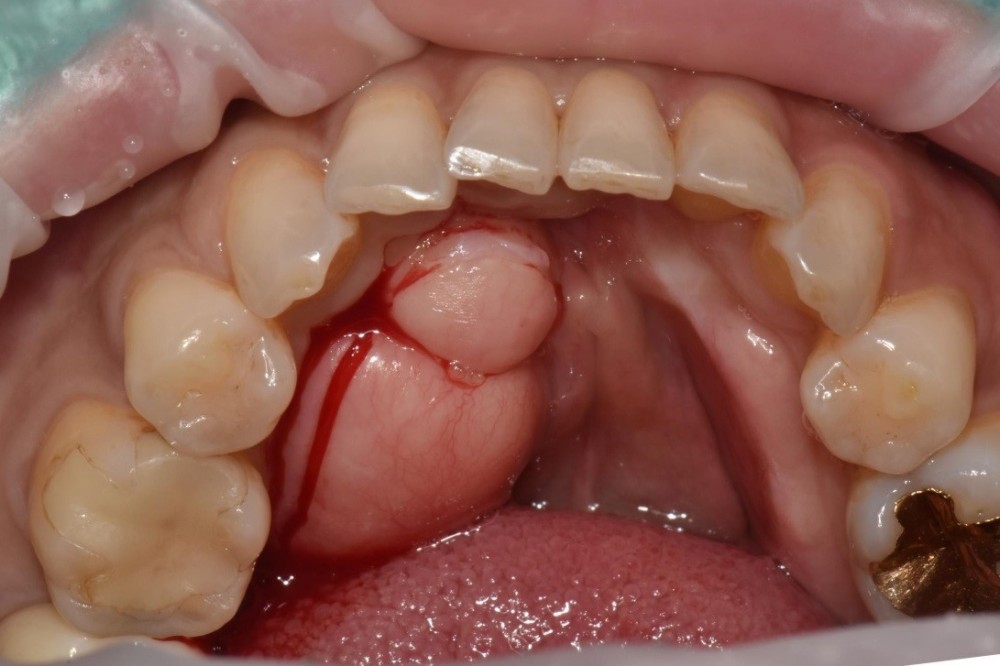

(Case2) 환자분은 음식물이 돌출된 뼈위로 쌓여 불편함이 지속되어 이를 해결하고자 내원하셨다고 하는데요. 사실 구강 건강에는 큰 문제가 없기 때문에 굳이 비용과 시간을 들여 제거하기 보다는 그대로 놔두시는게 좋으니 조금 더 신중하게 생각해보시라고 하며 권장드렸었지만 이후 환자분께서 생활이 너무 힘들다고 하여 제거를 진행한 케이스입니다.

앞서 사진과 마찬가지로 치료 중간 사진인데 치즐을 사용하여 골을 제거하는 것을 볼 수 있습니다.

치료 마무리된 사진을 보면 약간의 돌기가 남아있는게 보이지만 환자분이 느끼던 불편감은 거의 없어졌습니다.